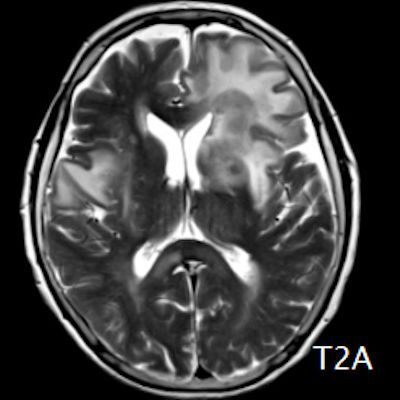

- (A) Her iki periventriküler beyaz cevherde aksiyel T2A, FLAIR serilerde hiperintens, T1A hipointens geniş ödem alanları (oklar) izlenmektedir. Sol frontalde T2A’da hipointens kitle lezyonuna (ok) dikkat ediniz.

- Genellikle supratentoriyal alanda, bazal ganglion, periventriküler beyaz cevher, orta hat ve korpus kallozum vb. yerleşme eğiliminde tek veya multipl kitleler şeklinde görülür.

- Kitleler çoğunlukla solid ve homojendir.

- MRG’de, lenfomalar tipik olarak T2A sekanslarda hipointens olup DAG’de belirgin difüzyon kısıtlanması gösterirler.